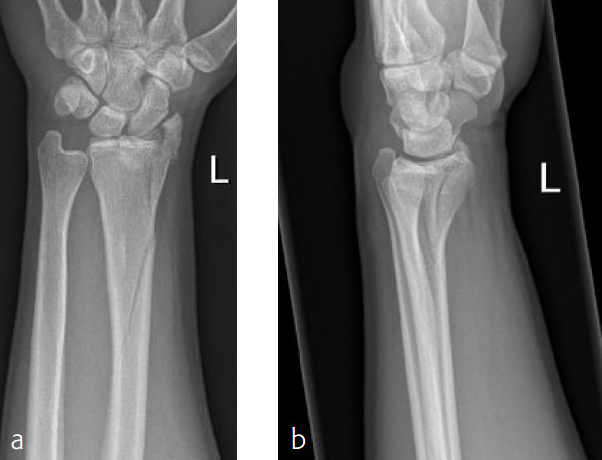

Fig 1ab Preoperative x-rays.

Fig 2ab X-rays postoperatively.

Fig 3ab X-rays 5 months postoperatively.